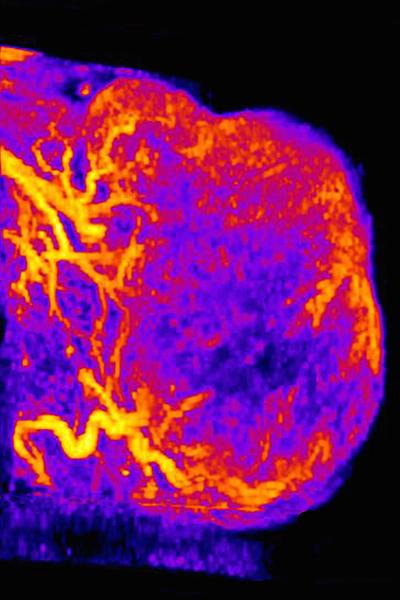

PECAM1 is an adhesion molecule. Scientists have known that endothelial cells use it to stick together to form blood vessels. When Dudley's team looked at blood vessels in tumors made of PECAM1-positive tumors, they found melanoma cells alongside noncancerous endothelial cells on the inside of vessels. "We don't think these new melanoma cells are just passively filling in gaps between endothelial cells in the tumor vasculature," Dudley said. "How they come to form blood-filled channels seems to be an active process that involves PECAM1."

Dudley and Dunleavey then teamed up with other scientists, including UNC's Paul Dayton, PhD, a professor in the Department of Biomedical Engineering, member of the UNC Lineberger Comprehensive Cancer Center, and co-author on the Nature Communications paper. Dayton's lab conducted ultrasound imaging studies showing that PECAM1-positive tumor blood vessels in mice had twice the vascular density of PECAM1-negative vessels. And the blood volume of PECAM1-positive blood vessels was 4 ½ times greater than PECAM1-negative vessels. This showed the researchers that these newly discovered PECAM1-positive melanoma cells had a real effect on the function of tumor blood vessels.